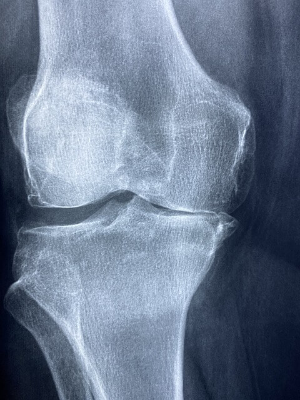

산후풍은 사람마다 증상이 다르게 나타날 수 있지만, 대표적인 증상은 다음과 같습니다. 전신 통증 및 관절통입니다. 손목, 무릎, 허리, 발목 등 관절이 뻣뻣하고 아픕니다. 손가락이 저리거나 감각이 둔해지는데 이 것은 손목터널증후군과 비슷한 증상입니다. 무릎을 구부릴 때 통증이 느껴지기도 합니다. 몸이 쉽게 피로하고 무기력함을 느낍니다. 조금만 움직여도 몸이 축 처지고 피곤함을 느낍니다. 근육이 뻣뻣하고, 쑤시는 느낌이 지속되며 날씨가 쌀쌀해지면 증상이 심해지는 경향이 있습니다. 땀이 많아지거나, 가만히 있어도 식은땀이 나거나, 반대로 너무 추위를 느낍니다. 출산 후 체온 조절이 어려워지는 경우도 있습니다. 간혹 통증이 지속되면서 불면증이나 불안감 증가하고 육아 스트레스와 겹쳐서 산후 우울증이 심해질 가능성이 있습니다. 출산 후 손목과 무릎 통증이 3개월 이상 지속되면 병원 검진이 필요합니다.